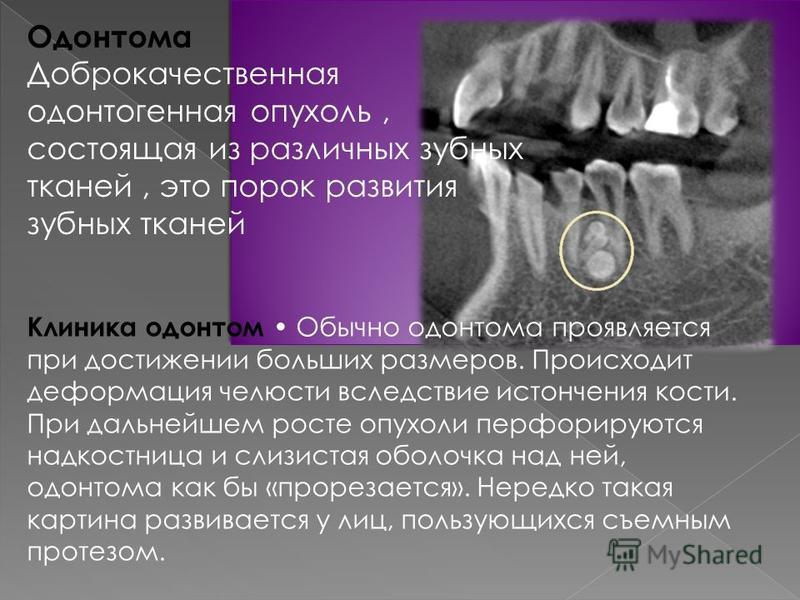

Раздел: Фотобанк решений